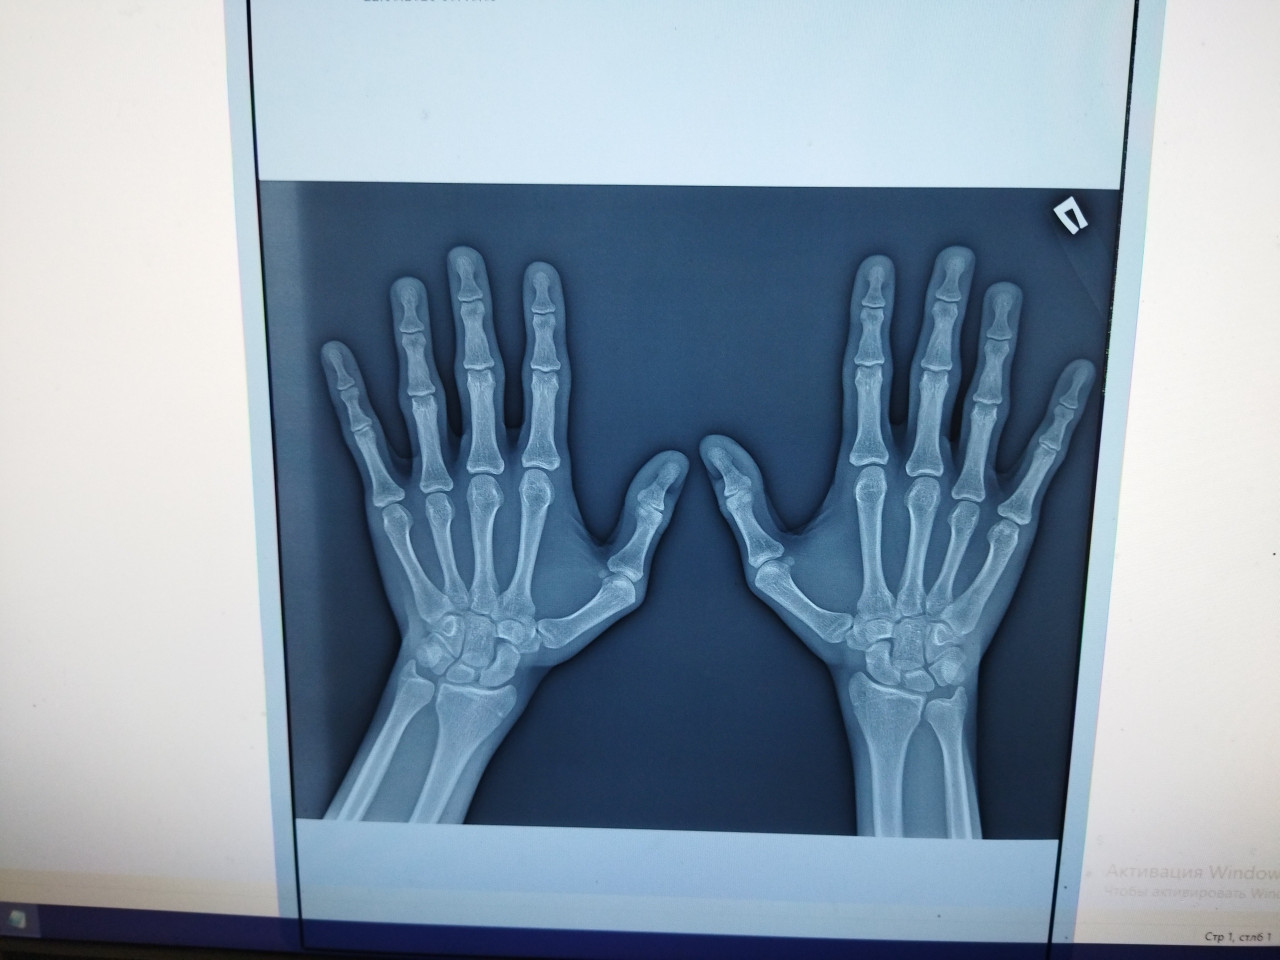

Здравствуйте, открыты ли у меня зоны роста на этом снимке? Мне 17 лет, рост 165см, перестал расти примерно в 14-15 лет. Если открыты, то сколько они могут быть открытыми (снимку пол года), и что можно сделать для увеличения роста?

Здравствуйте, Амир.

Описанием снимков занимается рентгенолог, а не эндокринолог. С описанными снимками обращайтесь к детскому эндокринологу. Я взрослый врач и работаю с пациентами старше 18 лет.